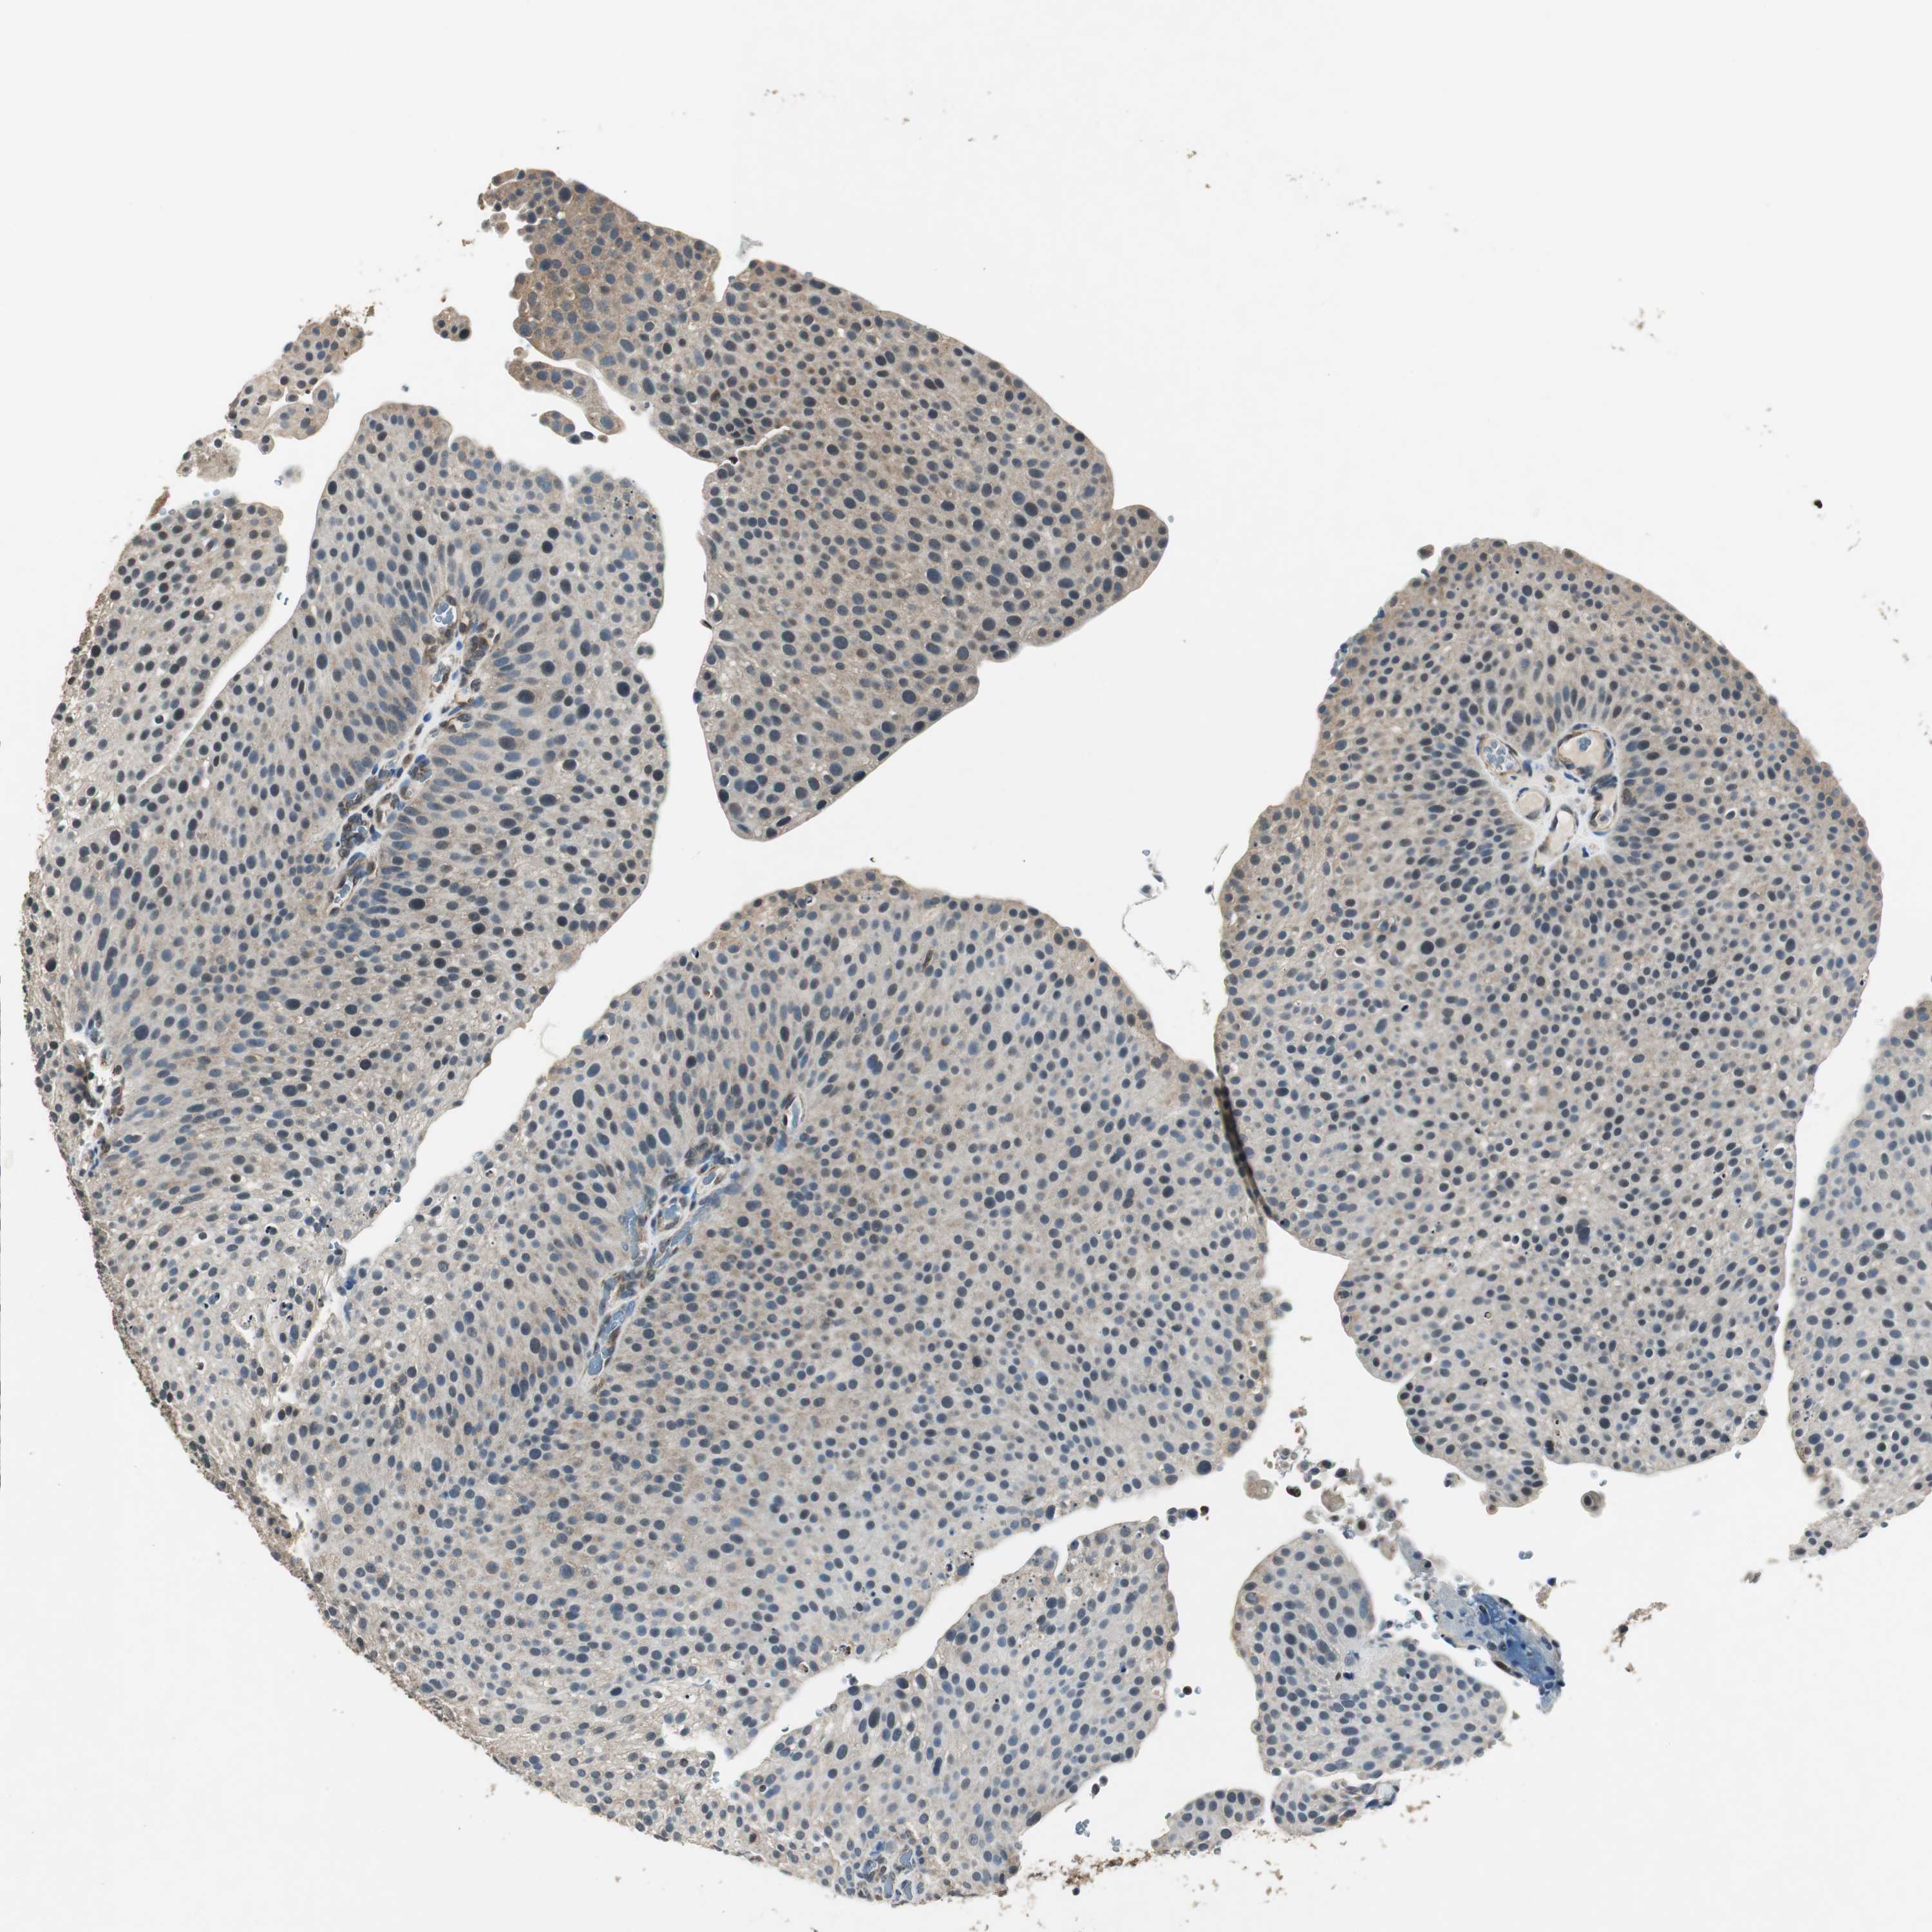

UROTHELIAL CANCER - Protein expressioni

A mouse-over function shows sample information and annotation data. Click on an image to view it in a full screen mode. Samples can be filtered based on level of antibody staining by selecting one or several of the following categories: high, medium, low and not detected. The assay and annotation is described here.

Note that samples used for immunohistochemistry by the Human Protein Atlas do not correspond to samples in the TCGA dataset.

Antibody stainingi

Antibody staining in the annotated cell types in the current human tissue is reported as not detected, low, medium, or high, based on conventional immunohistochemistry profiling in selected tissues. This score is based on the combination of the staining intensity and fraction of stained cells.

Each image is clickable and will lead to virtual microscopy that enables deeper exploration of all samples and also displays staining intensity scores, fraction scores and subcellular localization as well as patient and tissue information for each sample.

Antibody HPA006700

Staining

High

Medium

Low

Not detected

Intensity

Strong

Moderate

Weak

Negative

Quantity

>75%

75%-25%

<25%

None

Location

Nuclear

Cytoplasmic/membranous

Cytoplasmic/membranous,nuclear

Urothelial carcinoma, Low grade

Urothelial carcinoma, High grade